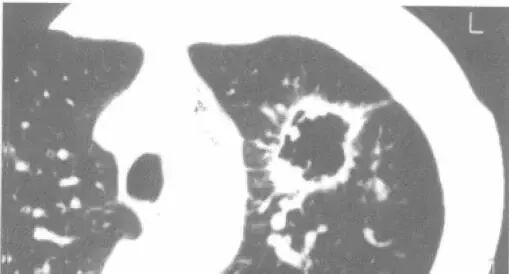

下面这个是什么?

首先,磨玻璃影,很可能是癌;假如里面有高密度的实性成分,则更可能是癌,并且,接近100%是腺癌

假如病理科报道:鳞癌。你可以要求病理科做免疫组化,再看看片子,不要冲动